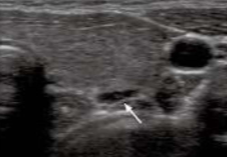

This thyroid nodule appears more likely to be:

Malignant

All of the following are ultrasound characteristics of a malignant thyroid nodule EXCEPT:

Complete fibrous capsule